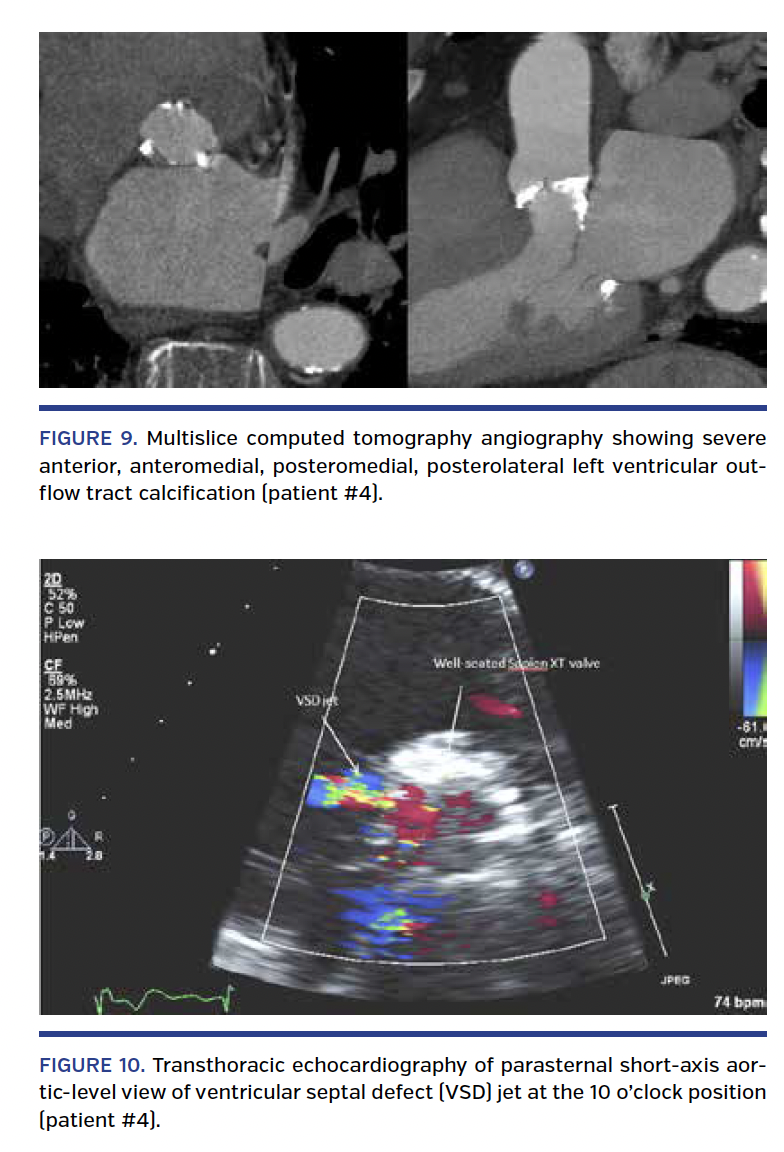

Patient #4. A 93-year-old man with very severe AS presented with complaints of progressive dyspnea with minimal exertion. His past medical history was notable for paroxysmal atrial fibrillation, heart failure with preserved ejection fraction, hypertension, chronic kidney disease, deep vein thrombosis, and myeloproliferative disorder. TTE showed an LV ejection fraction of 70% with peak and mean systolic gradients of 124 mm Hg and 61 mm Hg, respectively. AVA was calculated at 0.4 cm2. Coronary angiography revealed no obstructive CAD. Aortic annulus major and minor diameters measured at 27 x 18.6 mm, with an area of 460 mm2 on MSCT angiography. Area-derived diameter was 24.2 mm, and perimeter was 77.9 mm. Oversizing by CT-derived aortic annular area was estimated at 15.4% (Table 1). MSCT angiography demonstrated severe anterior, anteromedial, posteromedial, and posterolateral LVOT calcification (Figure 9). STS score was 9.37%.

He underwent successful deployment of a 26 mm Sapien XT valve (prepared according to standard protocol) via a transfemoral approach. There were no intraoperative complications. Repeat angiography showed trace to mild PAR. Postoperative TTE demonstrated mild PAR along the basal anteroseptum and the aorto-mitral continuity and a left to right shunt from the LVOT into the RV and a gradient of 94 mm Hg consistent with a restrictive perimembranous VSD seen at the 10 o’clock position in the parasternal short-axis view (Figure 10; Videos 10 and 11). No new conduction abnormalities were noted on ECG. Given the lack of symptoms at that time, he was managed conservatively. He was seen in clinic at 1-month follow-up and continued to be asymptomatic.